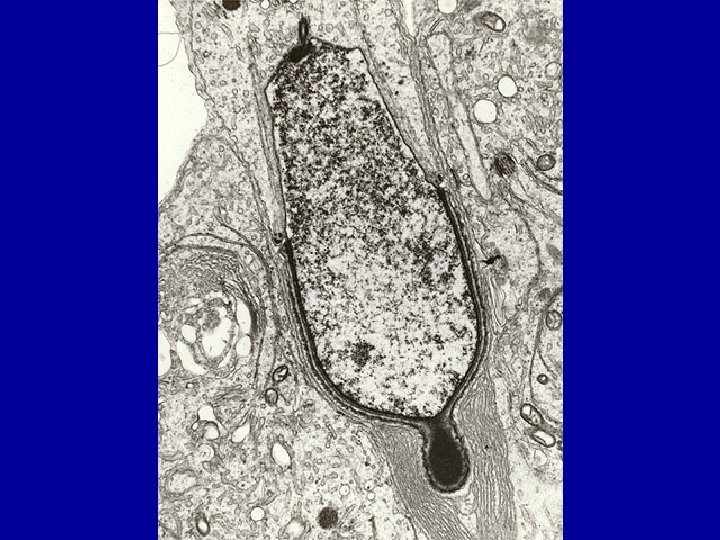

CELLULE DE LEYDIG * Microscopie Electronique Reticulum endoplasmique lisse+++ Mitochondries à crêtes tubulaires Inclusions diverses